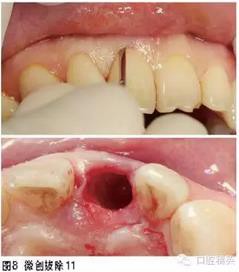

①11拔除后即刻種植即刻修復(fù)(預(yù)成臨時金屬基臺+樹脂全冠即刻修復(fù),6個月后,對11行個性化全瓷基臺+全瓷冠修復(fù));②21全瓷冠或瓷貼面修復(fù);③糾正深覆;④38、48擇期拔除。

治療過程